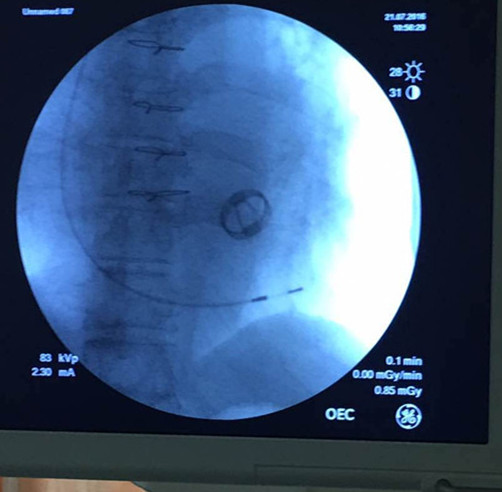

济宁市第一人民医院心内科孙晓斐教授成功的为1例巨大右心房患者植入心脏起搏器,属全国亦罕见。该患者为房颤合并三度房室传导阻滞,平均心率40次/分左右,但患者右心房巨大,心脏超声提示右心房大小46*96mm,右心室前后径22mm,心脏起搏器植入术需将起搏电极送至右心室,但因此类患者右心房巨大电极容易漂浮在右房,很难到达心室,即使电极到达心室因巨大右房的牵拉很容易弹出,导致电极脱位,在手术过程中,同样出现了电极难以到位(图1 电极在右房),到位后电极被弹出及电极脱位,但最终孙晓斐教授凭借30余年上千例心脏起搏器植入手术的经验,成功为患者完成手术(图2 电极在室间隔下部),解除病痛,康复出院。